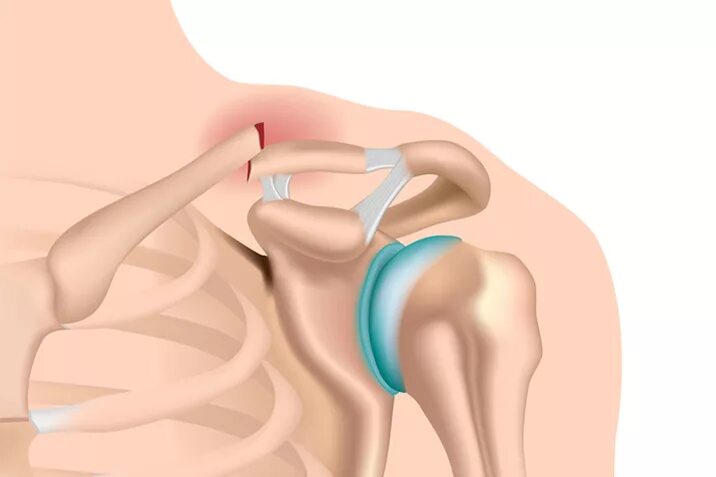

Хрустит ключица